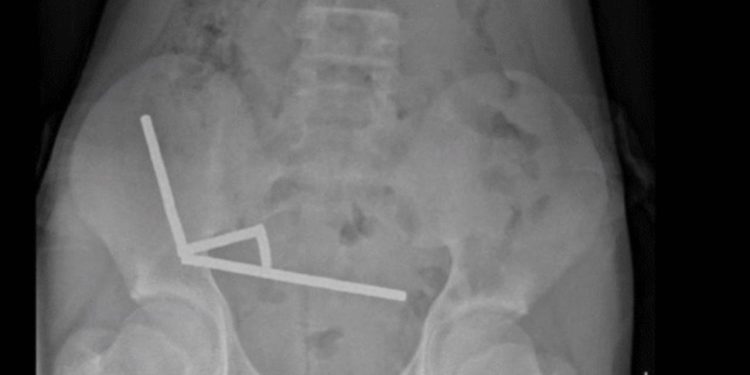

Röntgen görüntülerinde, çocuğun bağırsağında dört ayrı bölgede zincir halinde dizilmiş metal toplar görüldü. Ameliyatta bu zincirlerin ince bağırsak ve çekumda (kalın bağırsağın başlangıcı) birbirine yapışarak dokularda kan akışını engellediği ve “basınç nekrozu” denilen doku ölümüne yol açtığı tespit edildi.